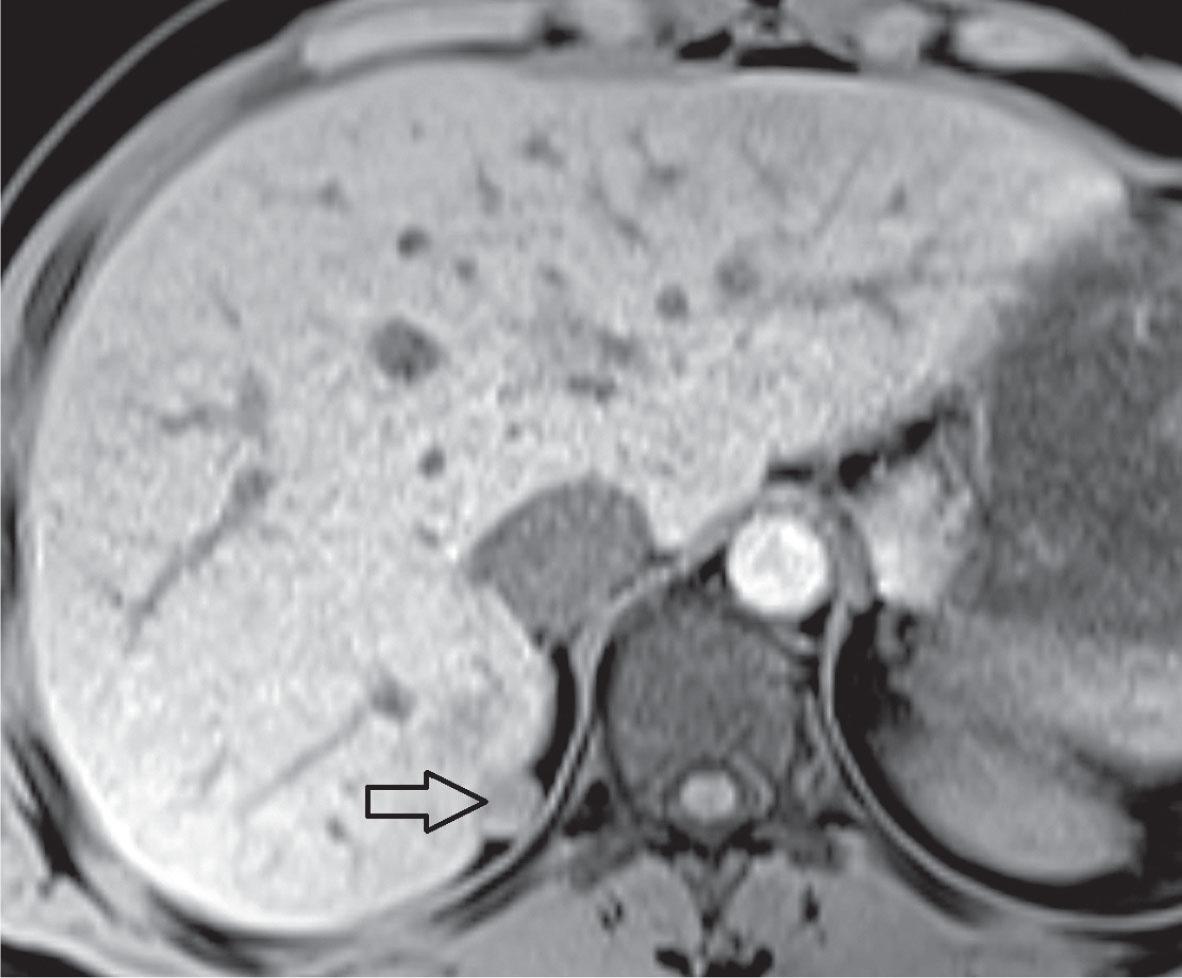

MRI; (A)hypointense hepatic lesion in T1 weighted image (WI); (B)T2 fast spin echo (FSE) WI: slightly high signal intensity of hepatic lesion.